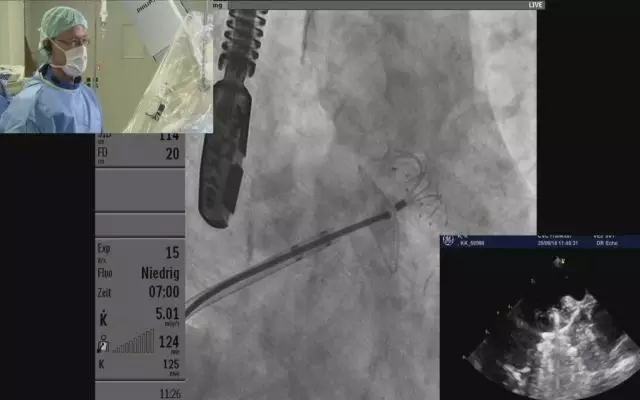

6月29日,由法兰克福心脏中心向大会主会场转播了一台选用彩神在线网信彩票-彩神通免费版下载-彩神8争霸vlll-彩神购彩购彩大厅-彩神软件陆立根免费版-彩神ll争霸3-彩神ll彩神8-彩神ll争霸彩票-拼搏在线彩神网网页版科技LAmbre™左心耳封堵器系统进行的高难度左心耳封堵手术。本例手术由法兰克福心脏中心Horst Sievert教授带领的团队完成。中华医学会心血管病学分会主任委员、复旦大学附属中山医院葛均波院士及另外四位专家现场观看了手术转播,并就手术处理策略及器械选择等话题与术者Horst Sievert教授进行了讨论交流。

接受手术的患者为一名77岁的男性,诊断为阵发性心房颤动。今年四月份服用利伐沙班和氯吡格雷后胃出血,血红蛋白仅有6g/dl,输血治疗后一直以来食欲不振。消化内科医生建议实施左心耳封堵手术。在TEE引导下穿刺和DSA下造影后,左心耳锚定区直径为17mm,具有丰富临床经验的Horst Sievert教授选用型号为LT-LAA-2430的LAmbre™左心耳封堵器对患者实施封堵,顺利完成整个手术。期间,Horst Sievert教授还与现场主持人进行了讨论,整个过程用时不到30分钟。葛院士对Horst Sievert教授精彩手术技艺给予高度赞赏。同时对彩神在线网信彩票-彩神通免费版下载-彩神8争霸vlll-彩神购彩购彩大厅-彩神软件陆立根免费版-彩神ll争霸3-彩神ll彩神8-彩神ll争霸彩票-拼搏在线彩神网网页版科技LAmbre™左心耳封堵器“双盘设计”、“封堵稳定”、 “型号规格齐全”、“能够适用于各种左心耳解剖结构”、“无需深入左心耳内进行释放”等特点给予了高度肯定。

(测量左心耳锚定区直径:17.16mm)